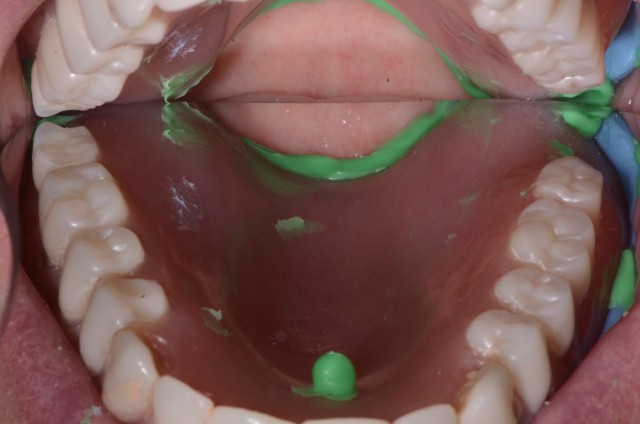

Mary Anne Salcetti | 8 years ago ›A Primer on Locator Abutments for Implant Overdentures

Here's a quick look at the benefits and complications surrounding the use of a locator abutment.